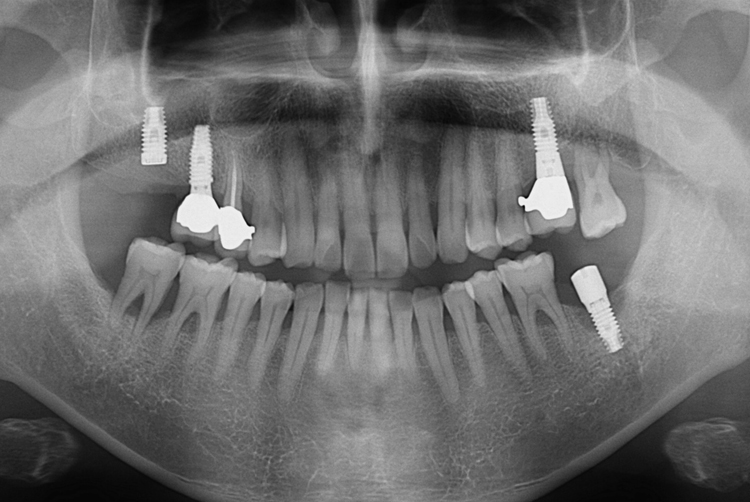

[임플란트] 어금니 임플란트

치료후 : 2018-12-07

세종치과는 많은 환자와 다양한 케이스를 바탕으로

항상 편안한 임플란트 수술을 제공하고자 노력하고,

오래동안 튼튼히 쓸 수 있는 임플란트 수술을 가장 큰 목표로 삼고 있습니다.